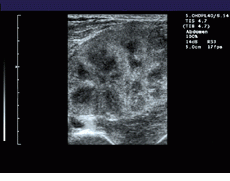

FIGURE 1. To extend the field of view (FOV) of ultrasound, the system registers sequentially acquired image frames and constructs a panoramic view of the extended FOV in real time. A comparision between a standard linear field of view of a renal transplant (bottom) and a wider, panoramic field of view (top) illustrates the effects of the process.

To increase the FOV in its Elegra system, Siemens combines the real-time imaging capability of modern ultrasound transducers with the ability to generate images over large fields of view. To do so, the system registers sequentially acquired image frames, estimates transducer motion, and constructs a panoramic view of the extended FOV in real time (see Fig. 1).